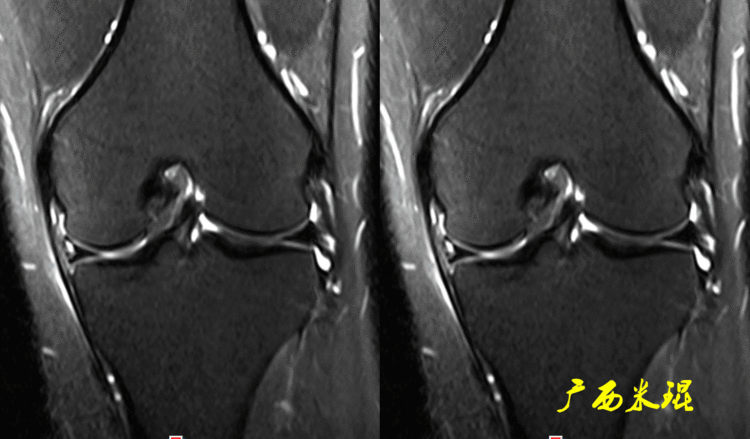

下面这张MR冠状位显示为内侧半月板后角的假桶柄,其母体(图片中内侧的那一部分半月板)并没有变小、形态及信号均正常。

下面这张MR冠状位显示为外侧半月板后角的假桶柄,尽管在髁间窝发现半月板信号,但其母体(图片中外侧的那一部分半月板)并没有变小、形态及信号均正常。